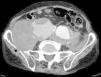

Paciente varón de 86 años, hipertenso en tratamiento con 2 fármacos, con historia de dolor lumbar con irradiación crural derecha de varios meses de evolución que se había controlado parcialmente con tratamiento sintomático. Su reumatólogo le había prescrito RM dorsolumbar que no llegó a realizarse ya que el paciente acudió antes a urgencias por aumento de la intensidad del dolor. En la analítica, hemoglobina 8,4g/dl, LDH 318 U/l, creatinina 1,29mg/dl, PCR 6,16mg/dl, VSG 24mm/h y leve hipoproteinemia. Ausencia de signos de inestabilidad hemodinámica. Se realizó una TC abdominopélvica con contraste por vía intravenosa que muestra aneurismas ilíacos aislados bilaterales>6cm (fig. 1) con rotura contenida del derecho (fig. 2), que desplazaba el músculo psoas (fig. 3) y horadaba el hueso ilíaco ipsolateral (fig. 4). El paciente es sometido a by-pass aortobifemoral pero lamentablemente fallece en el postoperatorio.

Los aneurismas ilíacos aislados, sin aneurisma aórtico asociado, son raros1. Son relativamente difíciles de identificar, ya que hasta un 40% de ellos se pueden presentar con rotura2. La tasa de incidencia de causas extraespinales de ciática es baja3. Igualmente, el aneurisma roto crónico constituye una entidad peculiar. Todas estas circunstancias se aúnan para que el diagnóstico, la mayoría de las veces, sea erróneo y tardío4. Suele tratarse de una rotura laterodorsal hacia las inserciones anteriores del psoas que contiene el hematoma, evitando la extravasación masiva pero no la infiltración de las raíces del plexo lumbosacro, lo que origina un dolor crónico lumbar con irradiación al miembro inferior5, siendo esta su presentación más frecuente6. El diagnóstico puede realizarse con TC abdominal7, pudiendo también visualizarse en la RM lumbar (corte parasagital)7,8. En cualquier momento de la evolución, el aneurisma puede sufrir una rotura aguda secundaria4. Este caso sirve para recordarnos, en nuestra práctica diaria, que la causa aneurismática puede estar implicada en los síntomas de ciática9.